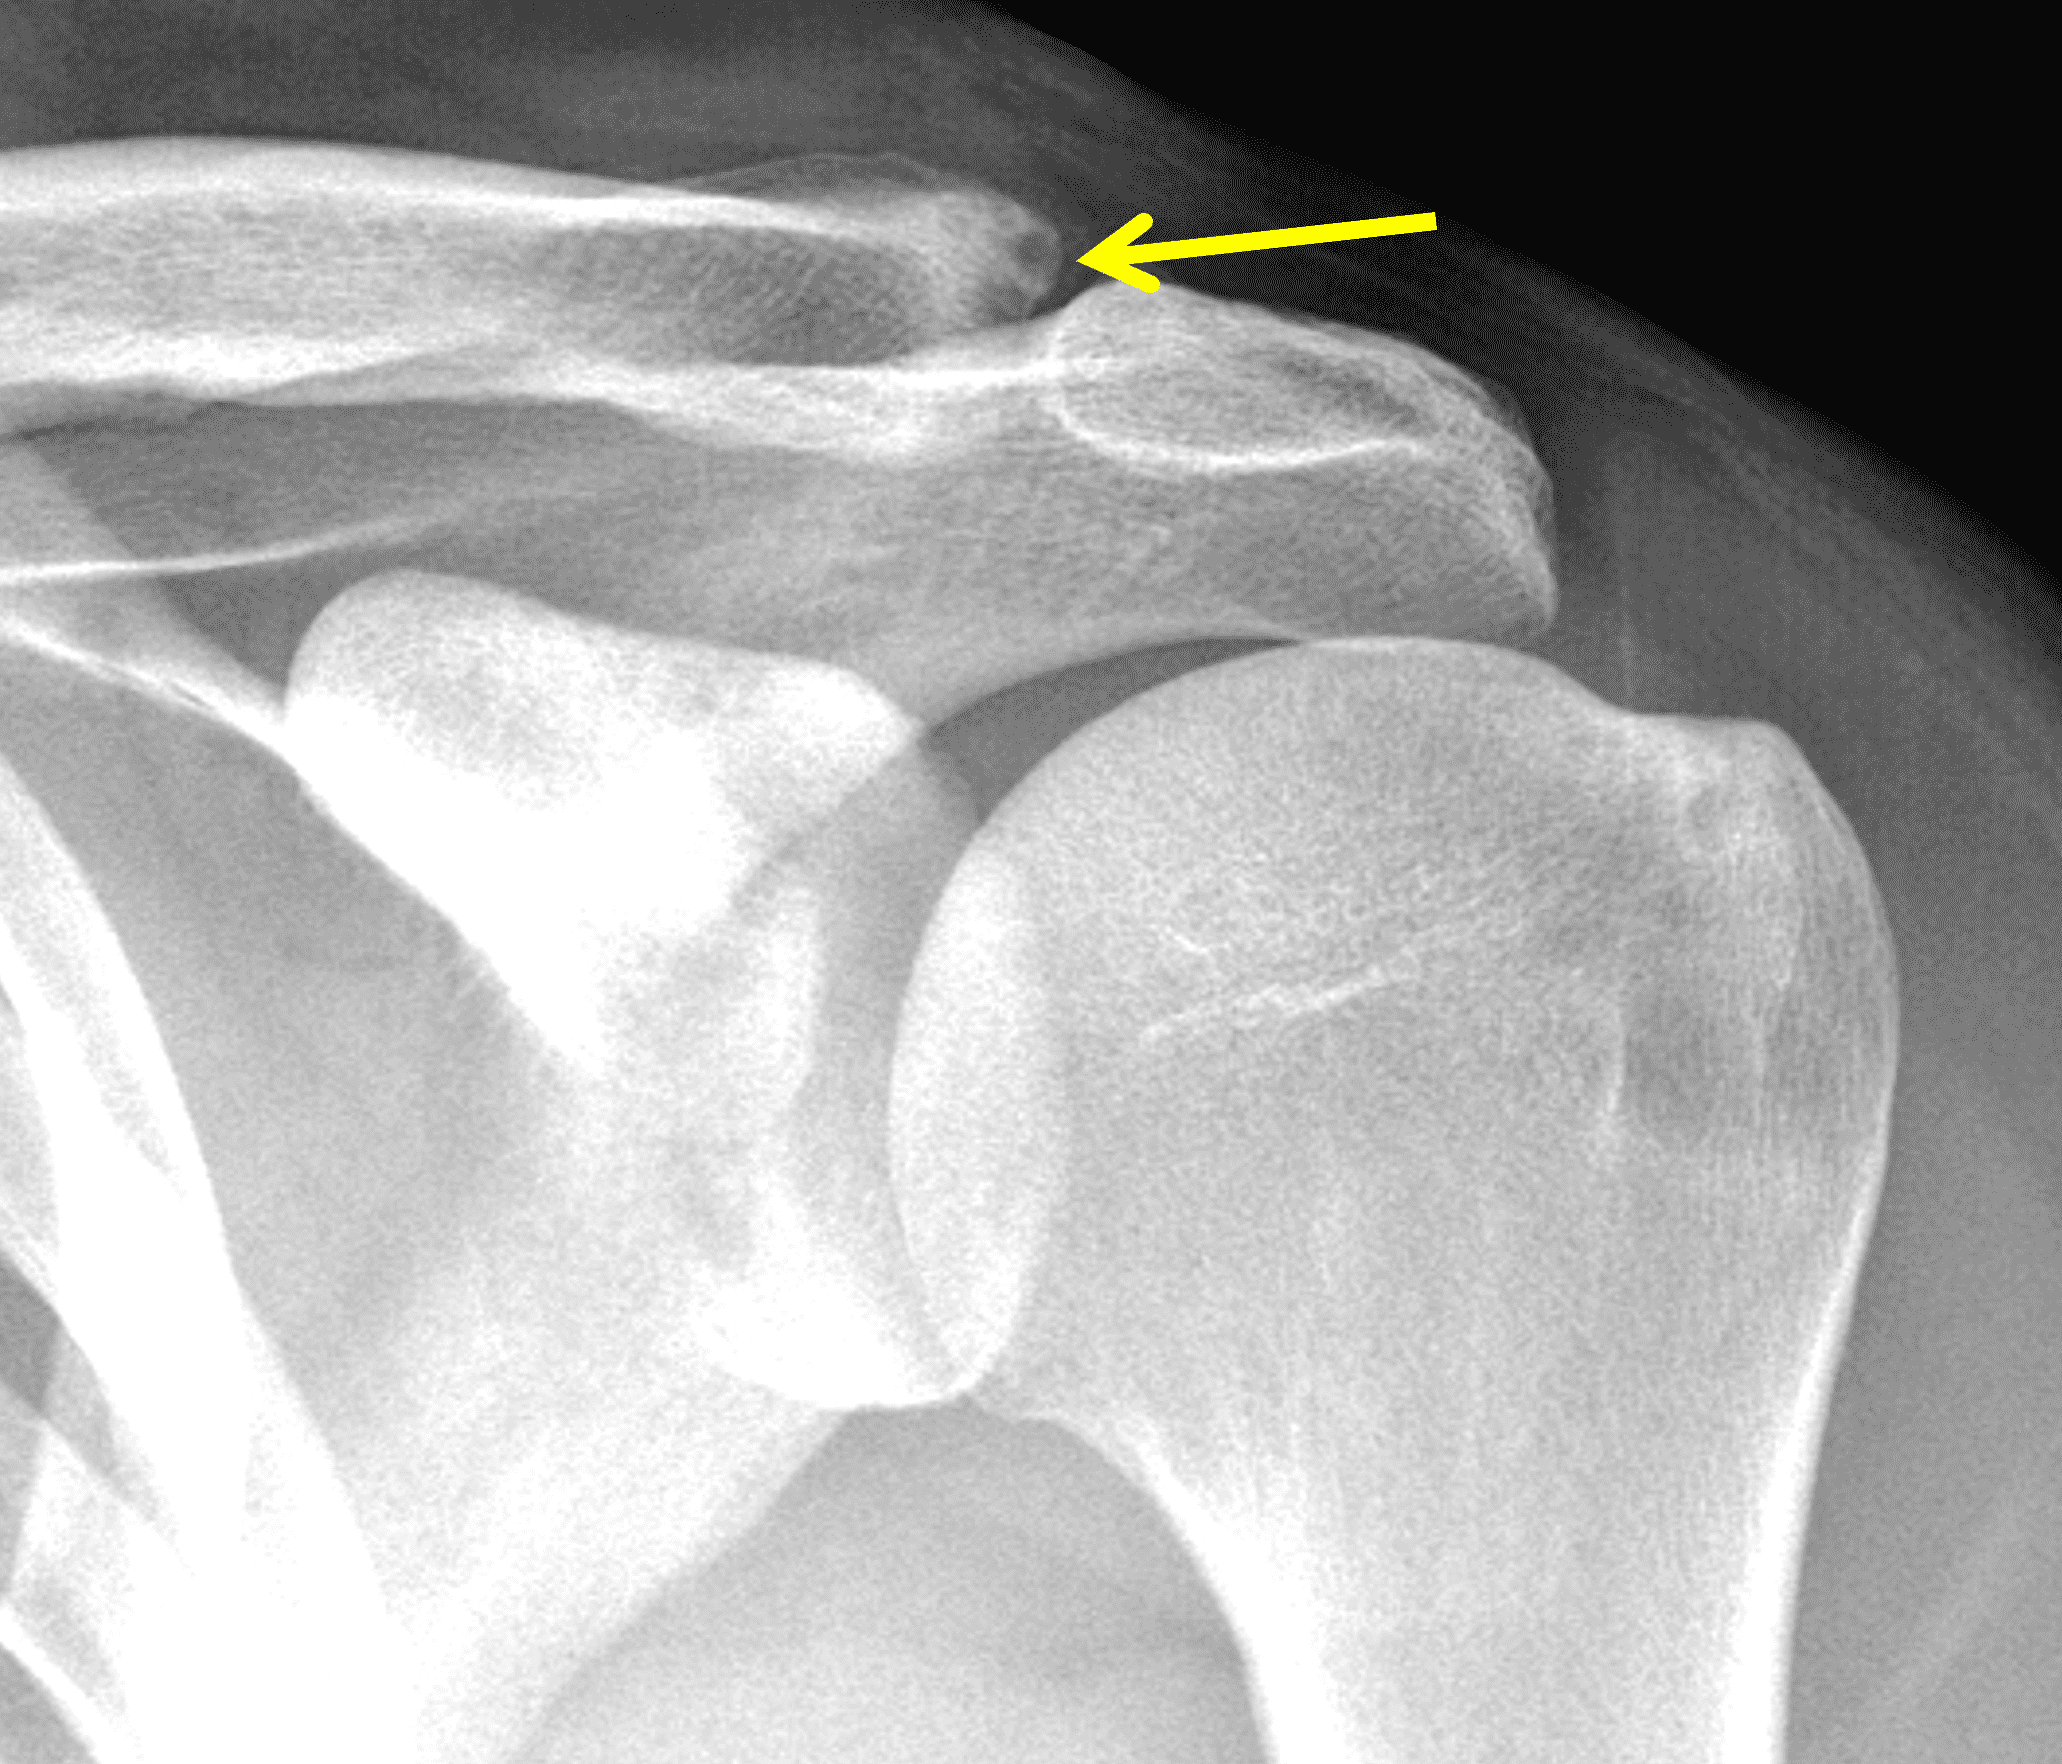

A 49-year-old male, avid weightlifter complains of chronic pain along the superior aspect of his right shoulder. He denies acute trauma. An AP radiograph (Figure 1A), as well as oblique coronal SPAIR (Figure 1B), axial fat-suppressed fluid sensitive (Figure 1C), and oblique sagittal T2-weighted images (Figure 1D) are shown. What are the findings? What is your diagnosis?

Radiographs: Initial radiographs may be normal or show features of other common unrelated AC joint pathology such as osteoarthritis. As inflammation and hyperemia in the distal clavicle progresses, bone density in the distal clavicle can decrease with indistinctness or discontinuity of the subchondral bone plate (Figure 3).  This so-called resorptive phase may also include frank erosions in the distal clavicle or a faint sclerotic line in the medullary space of the distal clavicle parallel to the bone end. Varying degrees of surrounding soft tissue swelling may be visible.  Later, during the late healing phase when symptoms have usually resolved, the distal clavicle may return to a normal radiographic appearance; a sclerotic line parallel to the distal bone end is visible after healing in some cases (Figure 4).  In patients with severe initial bone loss, re-cortication of the resorbed bone and erosions can occur leaving residual bone loss and contour defects in the distal clavicle. While it is typically not a primary modality for the diagnosis of DCO, CT demonstrates the same bone findings as radiographs.